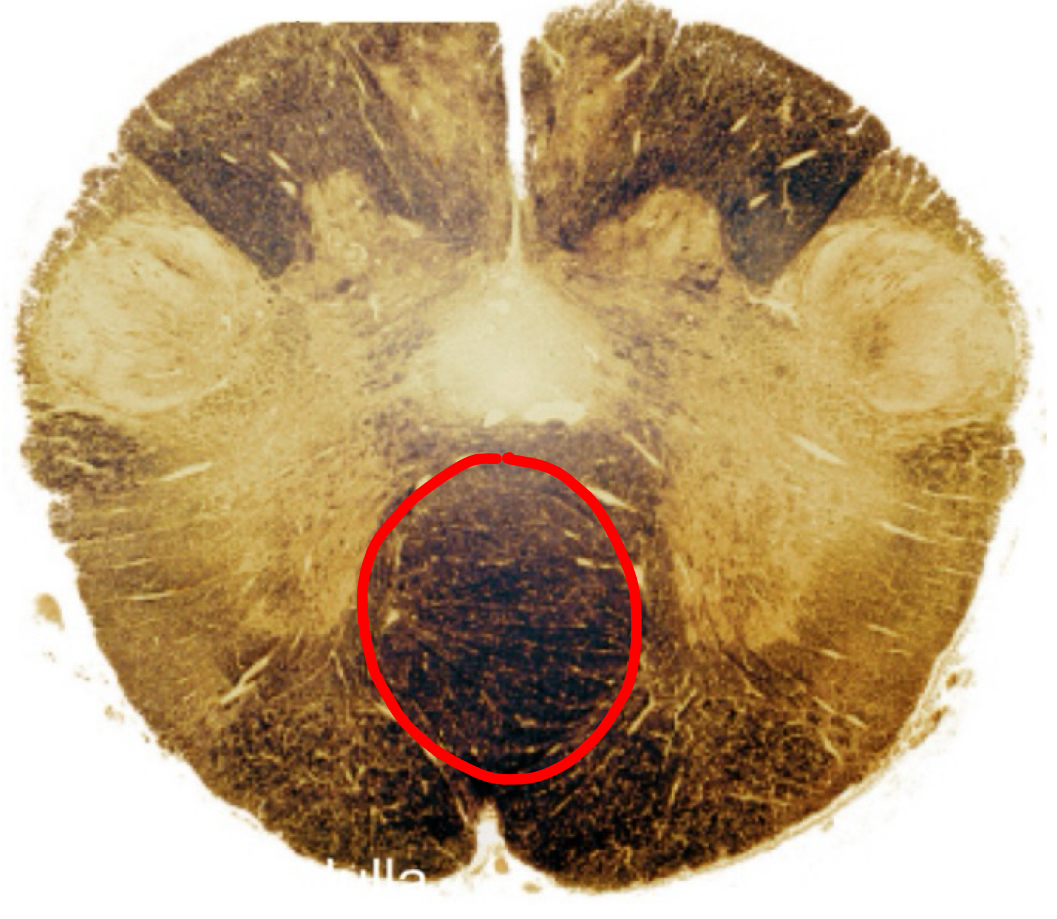

reticular formation rostral medulla